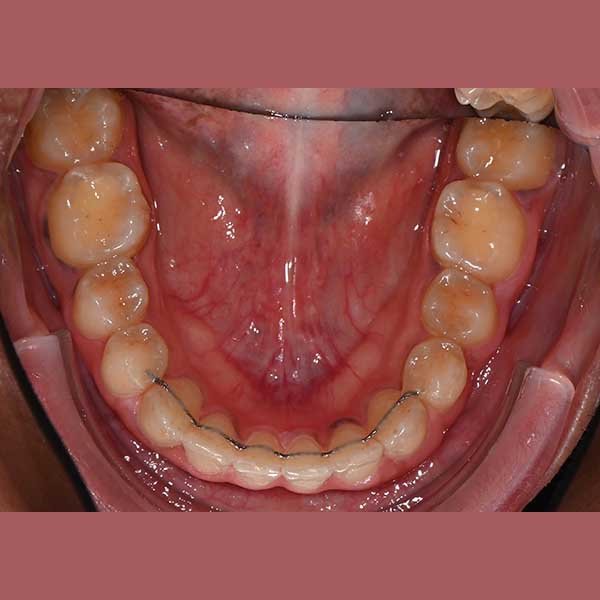

Case: Impacted upper canines – severe overlap – fixed orthodontics

By examining the case and taking X-rays, I observed the upper canines in her mouth, and an embedded lower premolar was observed too on the left side, I started the treat the case, but because of the old age of this lady, the upper canines and the left lower premolar did not erupt on their own after we extracted the temporary canines, and she had to pull them out by braces. As for the lower jaw; The canines were pulled back in place and the embedded premolar was orthodontically pulled.